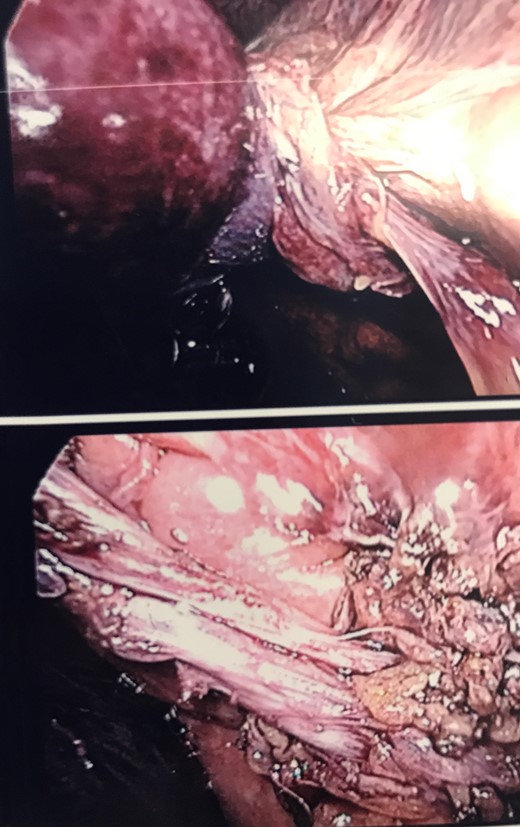

A Caucasian 92-year-old lady attended the emergency department with acute onset epigastric/right hypochondrial pain, waking the patient from sleep. The pain was described as being constant since onset and radiated through to her back. The pain was immediately followed by profuse and intractable vomiting. There had been no previous episodes of similar pain and she had been well in the preceding days. Her past medical history included an open appendicectomy, hypertension, GORD, previous TIA, left carotid endarterectomy, peripheral vascular disease and a L2 crush fracture. The patient denied fevers/rigors and had no recent history of lower urinary tract symptoms or altered bowel habit. The vital signs recorded for the patient were within normal limits and she was afebrile. On examination of the patient’s abdomen it was noted that the abdomen was soft and not distended, with diffuse tenderness down the right side. The gallbladder was also palpable to the right iliac fossa. The white cell count was mildly elevated at 13.2, while there were no electrolyte abnormalities and no renal or liver function derangement evident on blood tests. A CT scan of the abdomen and pelvis (Fig. 1) was arranged with contrast and was reported as showing a ‘distended gallbladder with prominent wall thickening and mild adjacent inflammatory change. The appearances are most consistent with cholecystitis’. An ultrasound was then performed that demonstrated a calculus together with minor gallbladder wall thickening but no evidence of biliary ductal dilatation. Thus, the patient was started on intravenous antibiotic therapy as per local guidelines for a presumed diagnosis of acute cholecystitis and admitted under the care of the general surgeons. The patient was reviewed on rounds the following morning and was noted to have increasing pain despite analgesia associated with tachycardia, tachypnoea and diaphoresis with a peritonitic abdomen. The white cell count was now elevated at 17.6 with a CRP of 198 and the liver function tests remained within normal limits. The patient was reimaged with a further CT abdomen/pelvis with contrast which was reported as showing ‘cholelithiasis and choledocholithiasis with intra and extra bile duct dilatation as well as marked gallbladder distension and pericholecystic fluid’. An emergency laparotomy was performed with findings on entry of a non-viable and gangrenous gallbladder secondary to gallbladder volvulus. The images below show the volvulus as well as the cystic duct and cystic artery after being detorted (Fig. 2). The patient was managed in ICU immediately postoperatively but medically fit for discharge after five nights in hospital.

Intraoperative imaging showing gallbladder volvulus and detorsion of the cystic duct and artery.